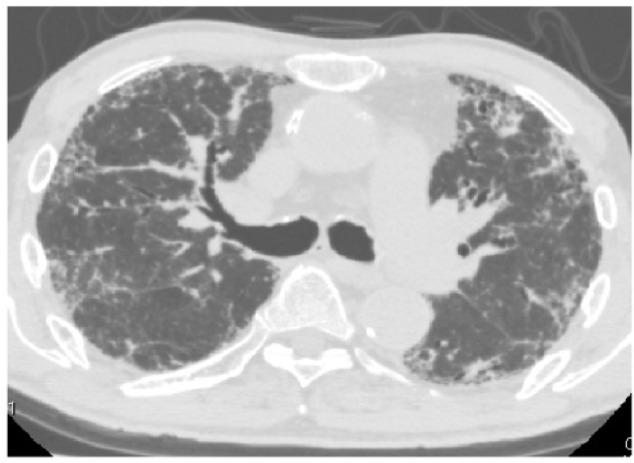

We report a case involving an 83-year-old man with interstitial lung disease who developed atypical pneumomediastinum caused by gas replacement of diminished fat. The patient presented with a complaint of worsening symptoms of respiratory difficulty since a diagnosis of chronic eosinophilic pneumonia 5 months back. He had been under observation with no particular treatment for 5 months. Computed tomography performed on admission revealed pneumomediastinum. When the current scan was compared with that obtained 5 months ago, it was evident that the fat surrounding the mediastinum had been replaced by gas density. There was no mediastinal enlargement, pneumothorax, or pneumopericardium. Because the patient was elderly, home oxygen therapy was initiated for the interstitial pneumonia with no steroid therapy. Computed tomography performed 10 months after discharge showed the reappearance of mediastinal fat and no evidence of gas density. This case is unique because the pneumomediastinum was distinct from spontaneous pneumomediastinum caused by alveolar air leaks and resembled the vacuum phenomenon caused by intervertebral disc degeneration.